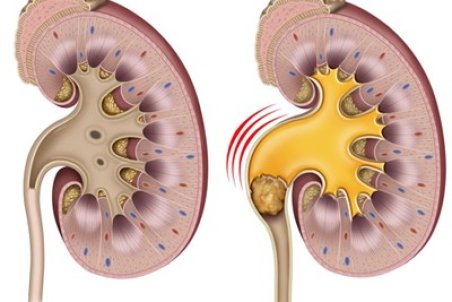

سنگ کلیه جسم سختی است که از موادشیمیایی در ادرار تشکیل شده. انواع متعددی دارد،اما همه دارای علائم مشابهی هستند که می تواند بسیار دردناک باشند،به ویژه اگر سنگ کلیه به مرور زمان رشد کرده باشد.

روشهای درمان سنگ کلیه شامل مصرف دارو، سنگ شکن برون اندامی (ESWL) و اورتروسکوپی میشود.

تشکیل سنگ های کلیه به طور معمول سال ها طول می کشد. علائم تا زمانی که سنگ ها در دستگاه ادراری شروع به حرکت نکنند، شرایطی که می تواند بسیار دردناک باشد، ظاهر نمی شوند.

تجمع بیش از حد املاح در کلیهها میتواند منجر به تشکیل سنگهایی به شکل کریستال شود که اگر دفع نشوند، میتوانند عوارضی چون عفونت یا آسیبهای کلیوی را بهدنبال داشته باشند.

معمولاً سنگهای کلیه کوچک، بدون بروز علائم و مشکلات خاصی دفع میشوند اما سنگهای بزرگتر در مجاری ادراری لانه میکنند و منجر به درد میشوند؛ اگر این سنگها دفع نشوند، میتوانند عوارضی چون عفونت یا آسیبهای کلیوی را بهدنبال داشته باشند.